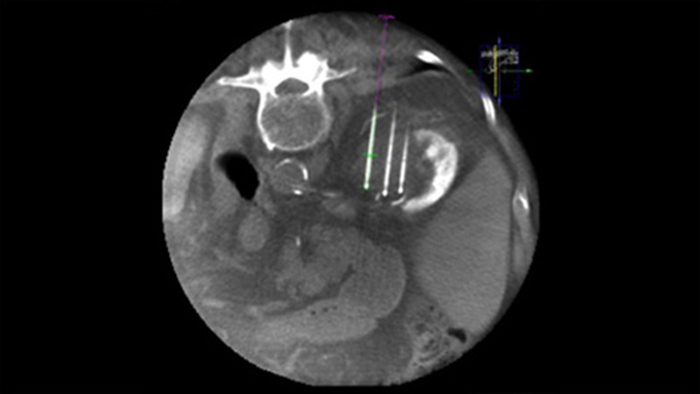

Чрескожная абляция (радиочастотная, микроволновая и криоабляция) — это зарекомендовавший себя малоинвазивный метод лечения опухолей почек, печени, легких и костей. Крайне важно определить границы опухоли, выбрать оптимальное количество игл и соответствующую траекторию для полного лечения опухоли без повреждения окружающих тканей. Прицельное продвижение к поражению при низкой дозе без изменения положения иглы увеличивает шансы на успех и снижает риск осложнений при биопсии или абляции. Проверить результат проведенной абляции можно с помощью 3D-визуализации, пока пациент находится на столе.

SmartCT Soft Tissue представляет собой метод получения КТ-подобных изображений, при котором процесс сопровождается пошаговыми инструкциями и расширенными инструментами 3D-визуализации и измерения; все элементы доступны на модуле сенсорного экрана прямо у стола.